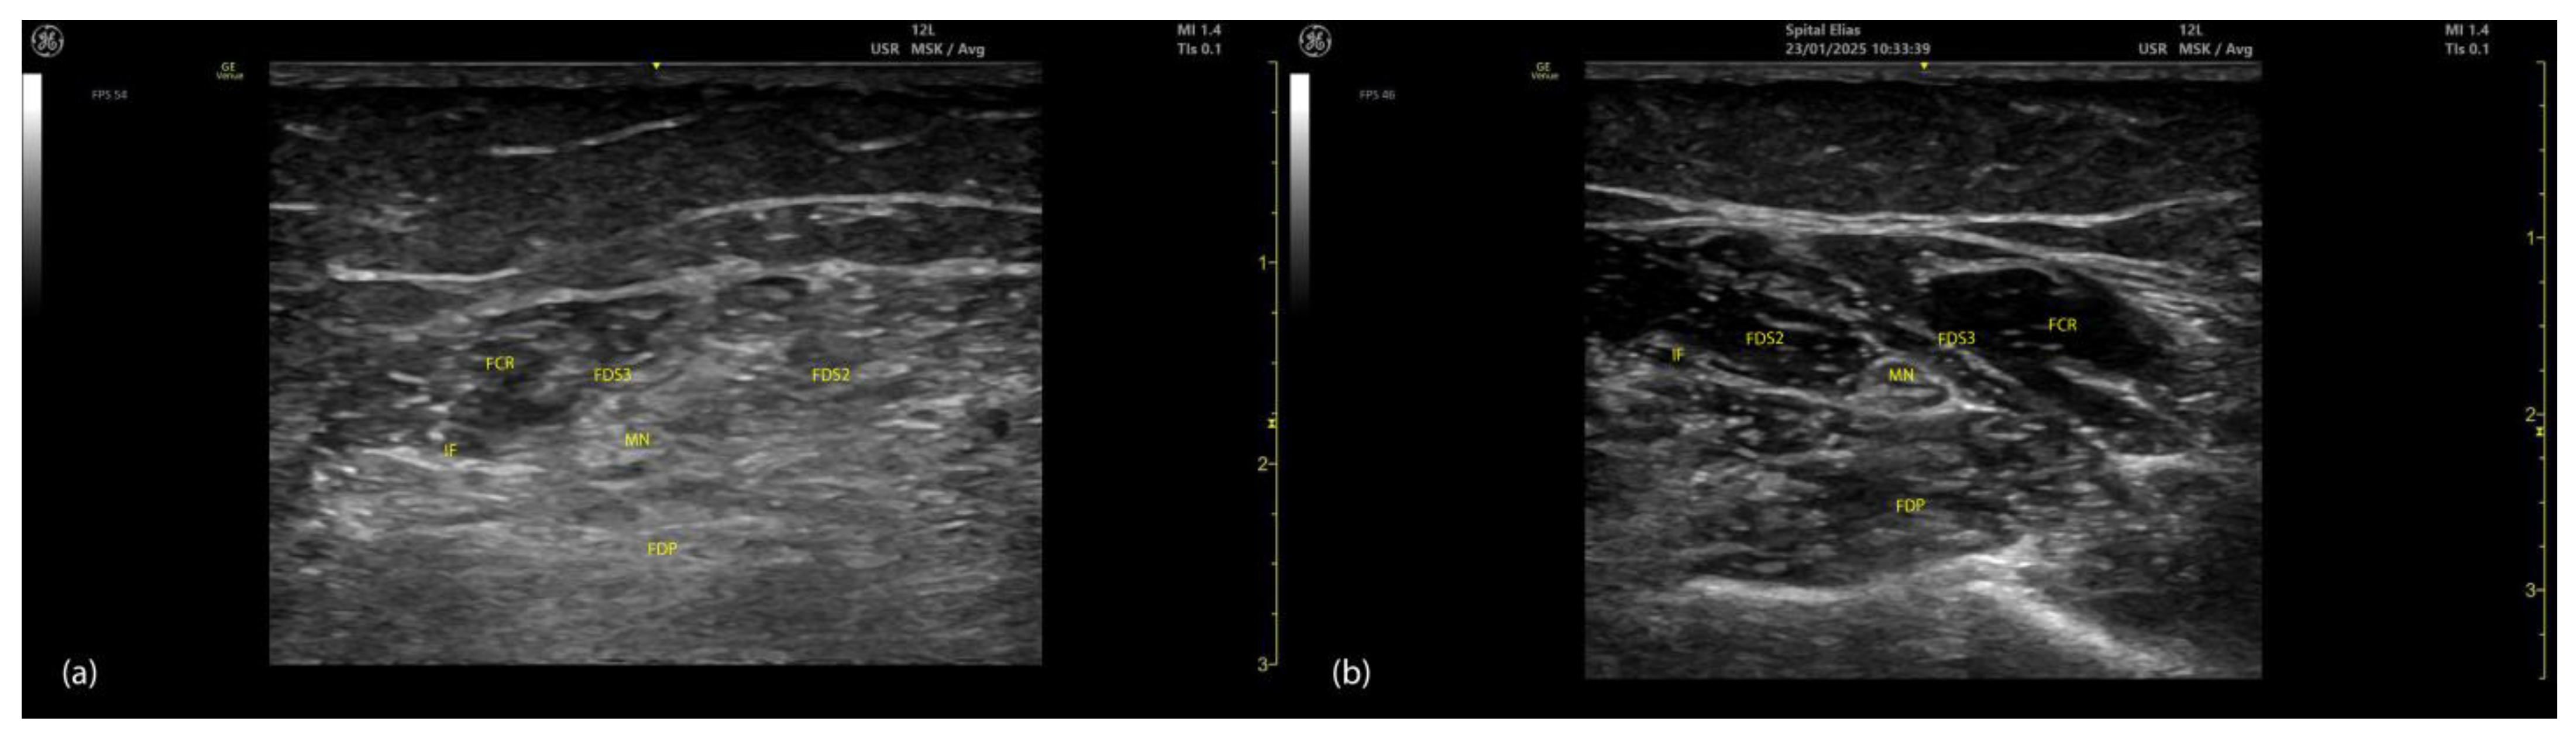

2.4.3. Key Ultrasound Landmarks (Figure 4 and Figure 5)

- Muscle position: At the mid-forearm, the FDS represents the second muscle mass from the cortical surfaces of the radius and ulna, moving from deep to superficial. Superficial to the FDS are the lateral FCR and medial FCU [29]. In the absence of US guidance, these adjacent muscles may be mistaken for the FDS, increasing the risk of injection errors.

- Median nerve: The median nerve is adhered to the deep surface of the FDS. At this level, the FDS and FDP are separated by the intermuscular fascia, which houses the median nerve, ulnar nerve, and ulnar artery [26].

- External fascia: FDS2 and FDS3 have a pronounced external fascia that distinctly demarcates them from adjacent muscle masses during BoNT-A injections, whereas FDS4 and FDS5 lack this feature.

- Dynamic evaluation (Video S3): The contraction of FDS muscle bellies corresponding to fingers II–V is observed during flexion of the metacarpophalangeal and proximal interphalangeal joints. A paradoxical arrangement of FDS2 and FDS3 bellies can be noted anatomically, as they appear inversely positioned medially and laterally relative to the median nerve [30]. Dynamic scanning proximal to the medial epicondyle reveals that the maximal thickness of FDS4 is located approximately 2–3 cm distal to the elbow crease, on the volar aspect of the forearm in the ulnar portion. At this level, the FDS4 is situated medial to the FCR and lateral to the FCU, following the line connecting the medial epicondyle to the pisiform bone [31]. A potential source of error in targeting FDS4 at this level is the palmaris longus (PL) muscle, which, if present, is located between the FCR and FDS4 muscle bellies. The PL is variably present in 74–97.5% of the population and is most commonly bilateral [32,33].

2.5.3. Key Ultrasound Landmarks (Figure 4 and Figure 5)

- Muscle position: At the mid-forearm, the FDP is the first muscle mass located directly superficial to the cortical surfaces of the radius and ulna [29].

- Intermuscular fascia: The FDP is separated from the FDS by intermuscular fascia that houses the median nerve, ulnar nerve, and ulnar artery [31].

- Median nerve: The median nerve adheres to the deep surface of the FDS and is positioned superficially relative to the FDP at this level [31].

- Internal fascia: FDP 2–5 is a single continuous muscle with four distinct tendons, corresponding to digits 2–5. Unlike some other muscles, the FDP does not have a pronounced fascia that demarcates separate muscle masses for each individual finger, making it a continuous muscular structure without clear fascial boundaries for each digit during BoNT-A injection.